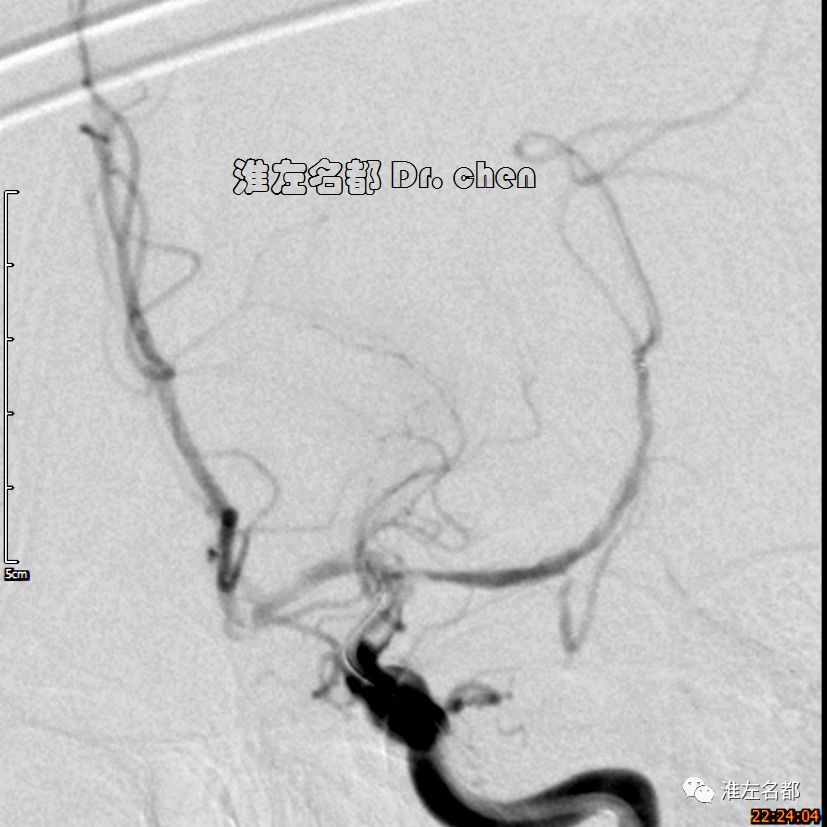

△经.035”泥鳅导丝将中间导管(Navien 058,125cm)送至左侧颈内动脉岩骨段,而后长鞘跟进至左侧颈内动脉,再经泥鳅导丝将中间导管送至海绵窦段,微导管(Rebar 27)在微导丝导引下进入左侧大脑中动脉M2段,造影证实位于真腔后,经微导管释放取栓支架(S AB 6*30mm)后造影:左侧颈内动脉远端充盈缺损,管腔严重狭窄;左侧大脑中动脉近端严重狭窄。

3.脑动脉夹层临床确诊依赖于影像学检测到典型夹层征象:内膜征/双腔征、长段不规则/丝线样狭窄、壁内血肿、夹层动脉瘤等。本患儿DSA显示左侧颈内动脉末端和大脑中动脉主干长段狭窄,且大脑中动脉主干狭窄呈“丝线样”,符合夹层影像学征象。

6.在夹层真腔得以基本恢复后,DSA于左侧颈内动脉末端、大脑前和中动脉近端均检测到典型“内膜征”,进一步确定了夹层诊断。